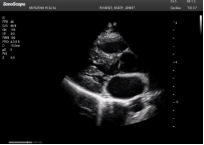

不同的探頭對(duì)應(yīng)于不同的臨床領(lǐng)域,不同的探頭頻率也應(yīng)用于不同的人體組織。超聲波在人體中的衰減與探頭頻率有關(guān),探頭頻率越高,穿透力越弱,分辨率越高,而探頭頻率越低,穿透力越強(qiáng),分辨率越低。因此在檢查淺表器官時(shí)應(yīng)選用高頻探頭,而檢查深部臟器時(shí)則選用穿透性強(qiáng)的低頻探頭。

(2)握持式:常用于劍突下切面的獲取。